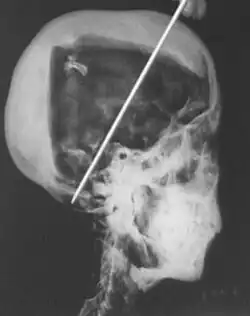

1968 X-rays

In 1968 R. G. Harrison, a professor of anatomy, used a portable X-ray machine to re-examine the mummy of Tutankhamun. Harrison quickly discovered that Carter had dismembered the mummy, something that is not mentioned in his publication but visible in photographs of the unwrapping. The mummy, surrounded by cotton wool and secured by modern bandages, had deteriorated since last photographed by Carter's team in 1926. The beaded skull-cap had disappeared, as had most of the skin on the head. The eyes appeared to be wide open as the eyelids had been destroyed, and the ears were broken off. The ribs had been sawn off and the front of the king's chest, including sternum and clavicles, had been removed. Stray beads from the large beaded collar were seen scattered in the torso on the X-rays. The limbs had been moved and further disarticulated, with the left hand and thumb of the right hand found in the sand under the body, and some of the digits on the hands and feet missing.[80][58][81] Although not mentioned by Harrison, the king's penis was also missing.[81] The additional damage to the mummy and the removal of the skullcap and collar likely occurred during the Second World War,[58] and components suggested to be from the collar have since appeared on the antiquities market.[82]

The X-rays revealed two levels of resin inside the skull. One was introduced when the body was lying on its back, pooling at the back of the head; the other when the head was tilted far back, settling at the top of the skull. Also present in the skull cavity were small bone fragments which Harrison initially believed to be the result of the embalming process. The fact that skull fragments were discovered led many to assume the king was murdered by a blow to the head, but the X-ray could not support or discredit this theory. His age at death was again estimated to be around 18, with a projected height in life of 168.9 centimetres (5 ft 6.5 in).[80] Serological analysis undertaken by the same team determined that Tutankhamun and the KV55 mummy had the same blood group, further indicating a familial relationship.[83]